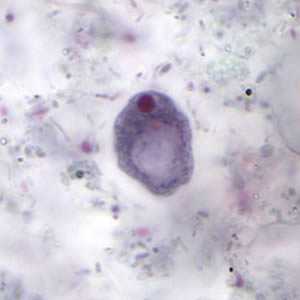

I. buetschlii cysts stained with trichrome.

Figure A: Cyst of I. buetschlii stained with trichrome. In this specimen, both the nucleus and large glycogen vacuole are visible.

Figure B: Cyst of I. buetschlii stained with trichrome. In this specimen, both the nucleus and large glycogen vacuole are visible.

Figure C: Cyst of I. buetschlii stained with trichrome. In this specimen, both the nucleus and large glycogen vacuole are visible (arrow).

Figure D: Cyst of I. buetschlii stained with trichrome. In this specimen, both the nucleus and large glycogen vacuole are visible.